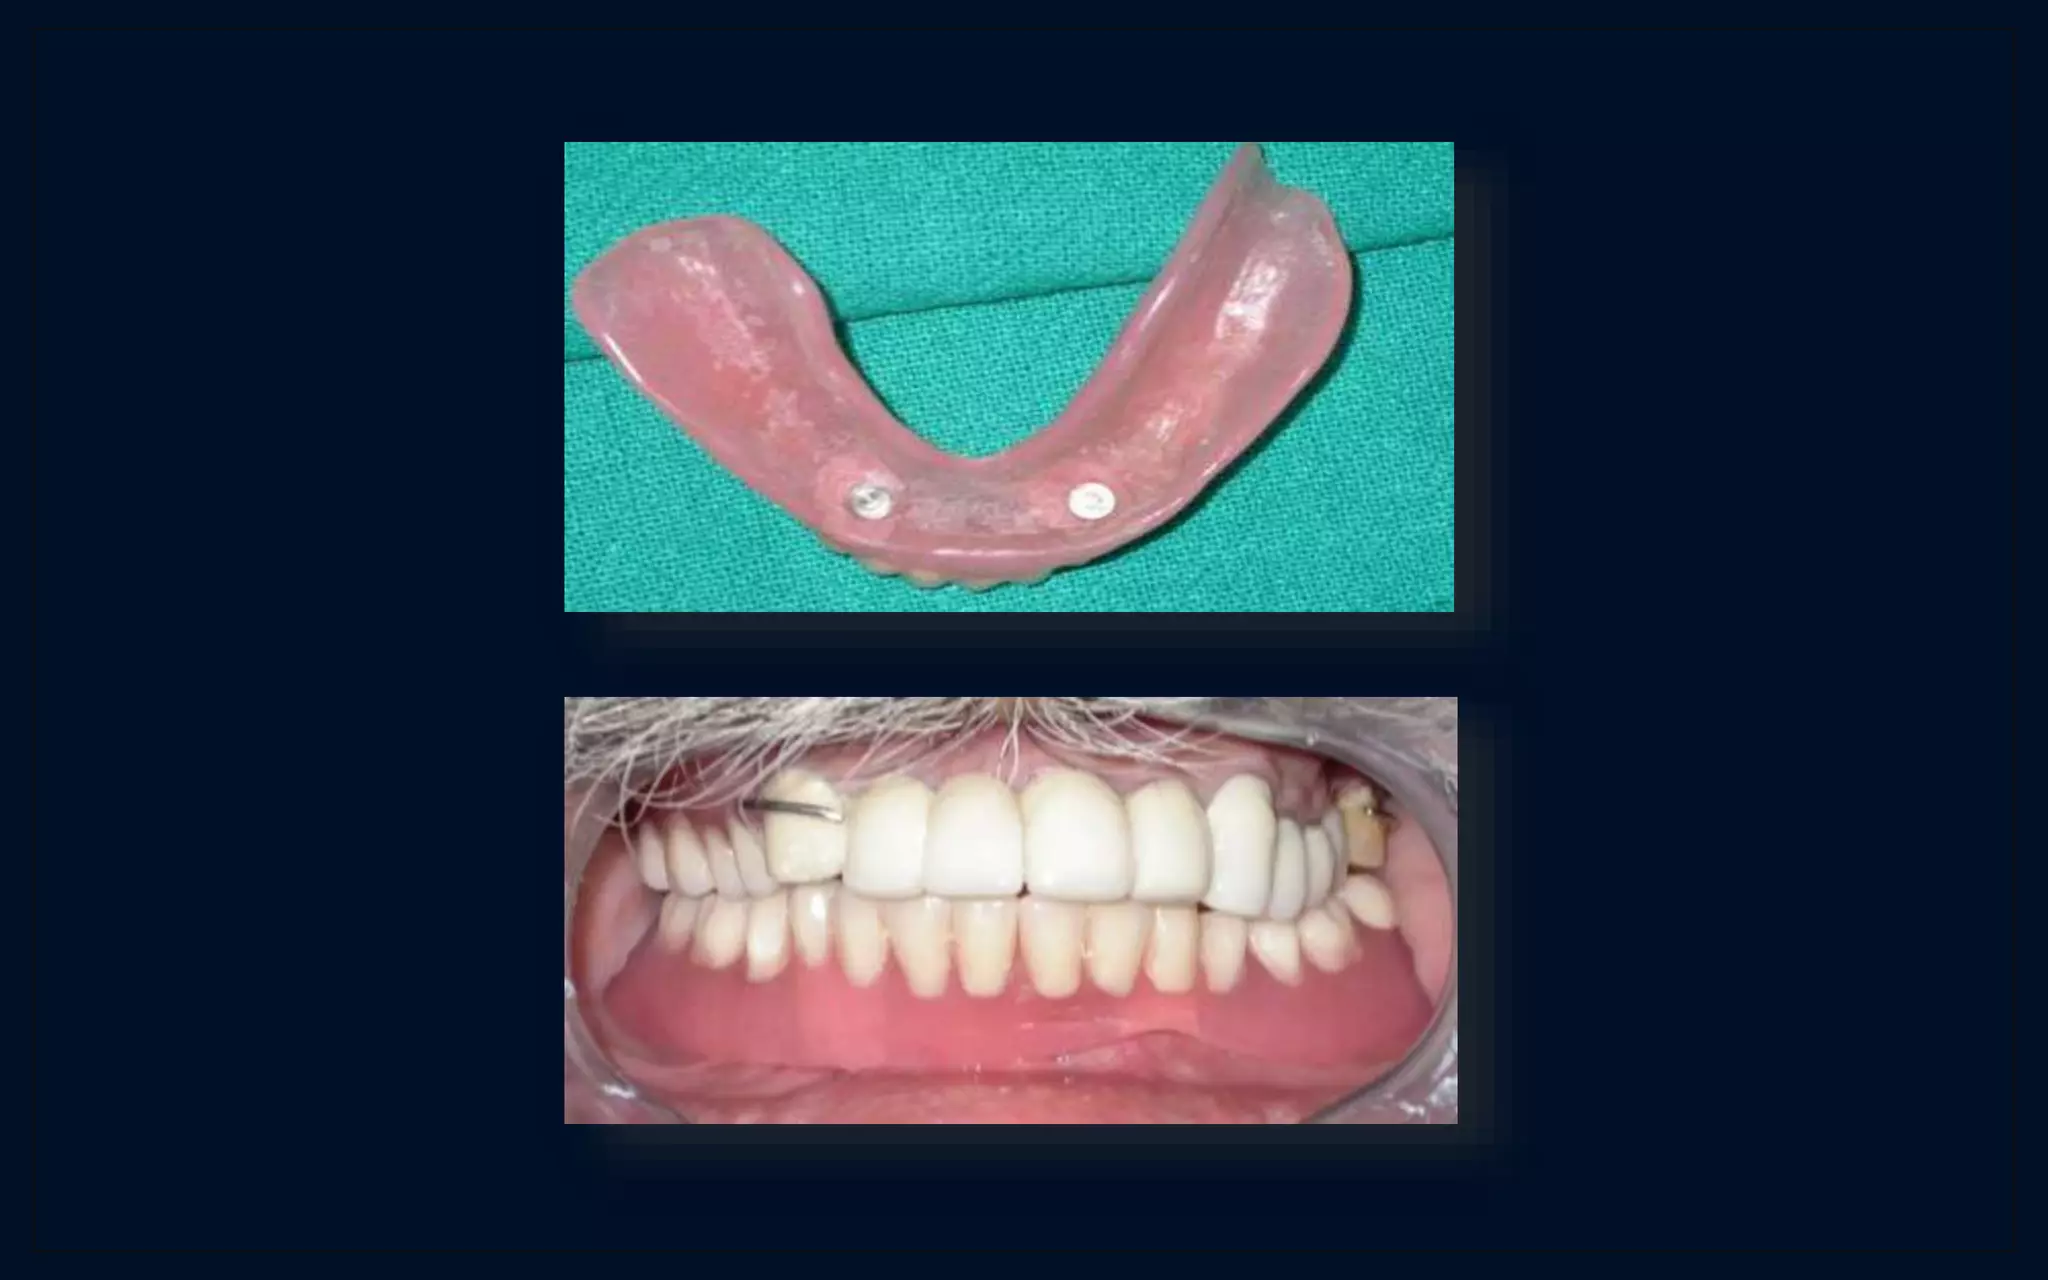

overdenture

P0ST-OPERATIVE….DAY - 2

P0ST-OPERATIVE….6 MONTHS